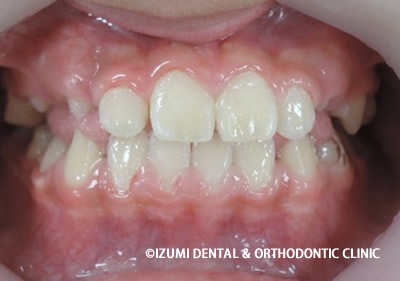

☆7歳3カ月 男子

乳臼歯にレジンを盛る事で咬み合わせの高さを治療していきます。

乳臼歯にレジンを盛る事で第一大臼歯の咬み合わせに隙間が出来ました。

咬合の高さをレジンによって高くすることで、第一大臼歯(6歳臼歯)が正常なところまで萌出できる隙間が確保されました。